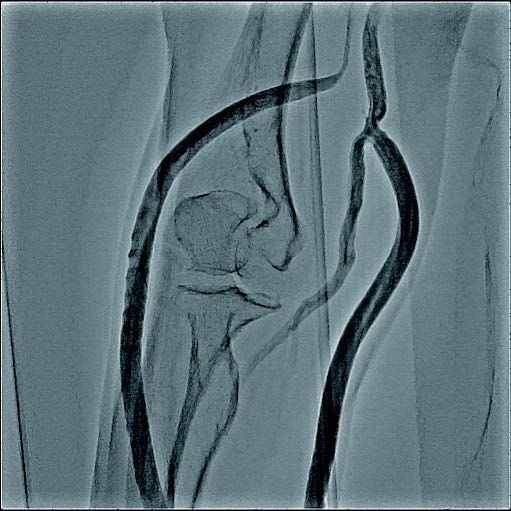

2021/04 バイアバーン® ステントグラフト留置

バイアバーン® ステントグラフト選択理由

人工血管の静脈側吻合部に短期間で繰り返す狭窄病変を認めていることが一番の理由であるが、当患者においては重要なもう一つの要因が存在する。

かつて使用されていた対側の人工血管を用いたシャントが、繰り返す血栓イベントにより開創し血栓除去を受けている。その過程で人工血管感染を起こし抜去術を余儀なくされていることから、今回の対象のAVG吻合部狭窄への修復には開創でなく、血管内治療での手技が好ましいと考えた。

バイアバーン® ステントグラフト留置の手技については、当施設では概ね毎回同じ手技を実施している。ステントグラフトの長さについては病変に依存するが、径については6 mmの人工血管に対して、7 mmのバイアバーン® ステントグラフトを留置している。

静脈とはいえ、透析患者においては硬化性変化が強い病変が多く、indentation を残さずに pre dilatation をかけておくことが重要と考えられる。そこで、径7 mmのバイアバーン® ステントグラフト留置前に、径6 mmの高耐圧バルーンにてしっかり拡張し、indentationを残さないことを確認した。バイアバーン® ステントグラフト留置後もバルーンでステント内、特に人工血管とのオーバーラップ部位にしっかり圧をかけて後拡張を行っている。

また、バイアバーン® ステントグラフトは、位置決めをした後の留置時に移動する事象は自施設で行った症例ではほとんど認めていないが、展開時のstabilityを保つため0.018 inchのサポートワイヤーを用いることが多い。当患者においても、上記手技を行い良好なinitial successを得られた。他症例もほぼ同一の手技で行っているがサイズなどで問題になった症例は、本稿の執筆時点では経験していない。